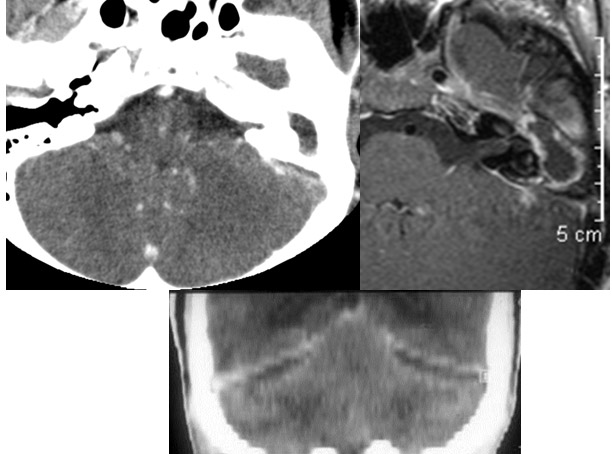

Case059

Findings

Extracranial Structures

There is edema%2fcellulitis surrounding the pinna, periauricular soft tissues, parotid gland or masticator and parapharyngeal spaces on either side.

Right Temporal Bone

External auditory canal is abnormal.

There is a subperiosteal abscess along the outer margin of the mastoid portion of the temporal bone.

There is dural reactive changesubperiosteal, epidural or subdural abscess long the roof of the mastoid or middle ear or the surfaces of the petrous portion of the temporal bone.

The ossicles; in particular the incus long process, the incudostapedial joint and stapes are eroded or displaced.

The facial canal and nerve are abnormal.

The petrous apex is abnormal.

The inner ear, in particular the lateral semicircular canal and the cochlea are eroded or otherwise abnormal.

Left Temporal Bone

There is dural reactive changesubperiosteal, epidural or subdural abscess along the roof of the mastoid or middle ear or the surfaces of the petrous portion of the temporal bone.

Intracranial

There is gas in the subarachnoid space or otherwise intracranial.

There is evidence of thrombosis, thrombophlebitis or other occlusive or inflammatory process of the sigmoid sinus, transverse sinus, the vein of Labbe’ or jugular bulb

There is evidence of thrombosis, thrombophlebitis or other occlusive or inflammatory process of jugular vein.

There is dural reactive change along the floor of the middle cranial fossa or along the inner surfaces of the petrous portion of the temporal bone.

There is a subperiosteal, subdural or epidural abscess along the floor of the middle cranial fossa or along the inner surfaces of the petrous portion of the temporal bone.

There is likely meningitis involving the inferior temporal lobe or adjacent cerebellum

There is likely cerebritis involving the inferior temporal lobe or adjacent cerebellum.

There is brain edema and/or evolving abscess present or, specifically, involving the inferior temporal lobe or adjacent cerebellum.

There is obstructive hydrocephalus - either intra or extra ventricular or signs of raised intracranial pressure.